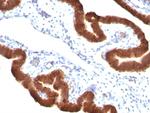

Cytokeratin 19 (KRT19) (Pancreatic Stem Cell Marker) Monoclonal Antibody (KRT19/799, KRT19/800)

Cytokeratin 19 is part of a subfamily of intermediate filament proteins and are characterized by a remarkable biochemical diversity, represented in human epithelial tissues by at least 20 different polypeptides. Cytokeratins range in molecular weight from 40-68 kDa and isoelectric pH between 4.9 - 7.8. The individual human cytokeratins are numbered 1 to 20. The various epithelia in the human body usually express cytokeratins which are not only characteristic of the type of epithelium, but also related to the degree of maturation or differentiation within an epithelium. Cytokeratin subtype expression patterns are used to an increasing extent in the distinction of different types of epithelial malignancies. The cytokeratin antibodies are not only of assistance in the differential diagnosis of tumors using immunohistochemistry on tissue sections, but are also a useful tool in cytopathology and flow cytometric assays. For example, cytokeratin 19 is not expressed in hepatocytes, therefore, it is useful in the identification of liver metastasis.